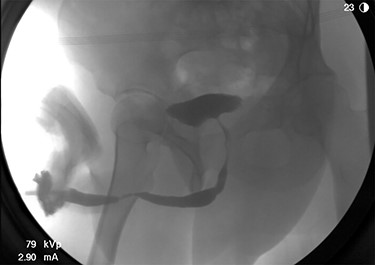

The patient underwent further evaluation with imaging including renal ultrasound, which was normal. Flexible cystourethroscopy demonstrated a circumferential urethral mass concerning for urothelial carcinoma (Fig. 1), which was biopsied with histopathology negative for urothelial carcinoma but positive for amyloid protein deposition. Examination of the external genitalia was unremarkable and there was no palpable induration along the ventral penile shaft. Systemic workup for additional manifestations of amyloidosis was negative. Imaging with retrograde urethrography (RUG) demonstrated an ~2 cm segment of urethral stenosis in the penile urethra (Fig. 2).

Endoscopic visualization of circumferential amyloid protein deposition causing urethral luminal narrowing.